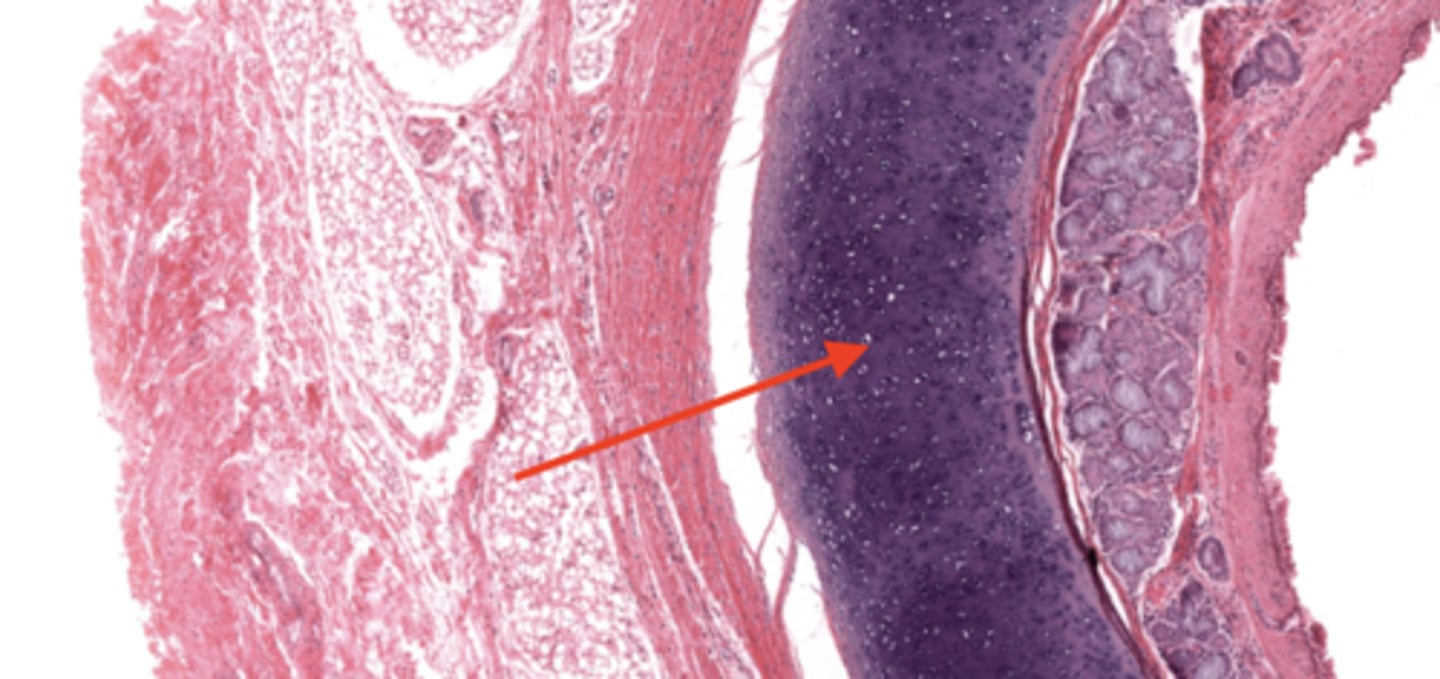

trachea

tracheal cartilage

respiratory epithelium